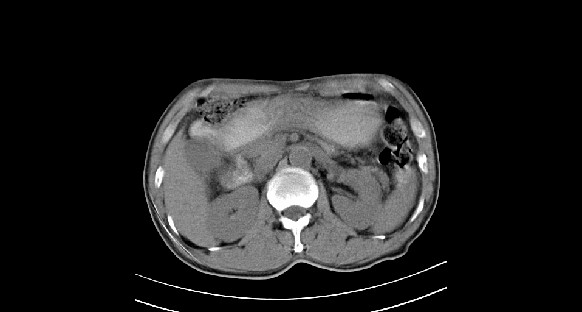

男性,70岁,体检b超发现左肾占位,请各位战友发表一下观点

左肾有两个病灶,且较大的病灶内可见点状钙化灶,增强扫描边缘也是呈渐进性强化,中央部分未见明显强化